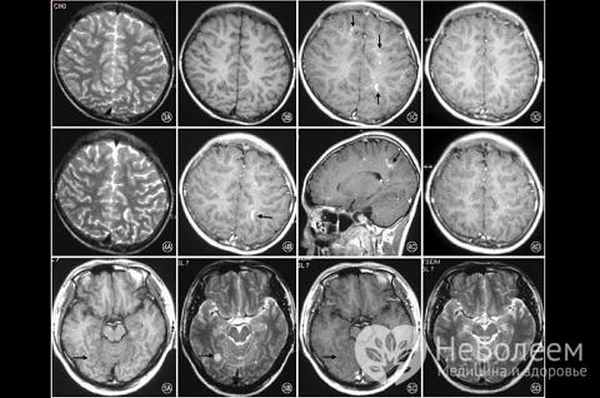

У пациентов с инфекцией мозга, вызванной B. mandrillaris на КТ и МРТ (оба исследования с контрастированием) обычно обнаруживаются множественные узловые повреждения с кольцевидным усилением. Кровоизлияния внутри повреждений являются важным рентгенологическим признаком. В СМЖ – повышенное число лейкоцитов (преобладают лимфоциты), уровень глюкозы в норме или понижен, а уровень белка часто значительно повышен. B. mandrillaris определяется редко. Микроскопическое исследование плюс ПЦР и иммуногистохимические методы могут идентифицировать B. mandrillaris при проведении биопсии очаговых поражений головного мозга или кожи.

У пациентов с инфекцией мозга, вызванной Acanthamoeba, на КТ с контрастом и МРТ могут обнаруживаться одно или несколько объемных повреждений с кольцевидным усилением, наиболее часто в височной и теменной долях. В спинномозговой жидкости (СМЖ) - повышенное число лейкоцитов (преобладают лимфоциты), но трофозоиты наблюдаются редко. Эти исследования помогают исключить другие возможные причины, но обычно не способны подтвердить диагноз.